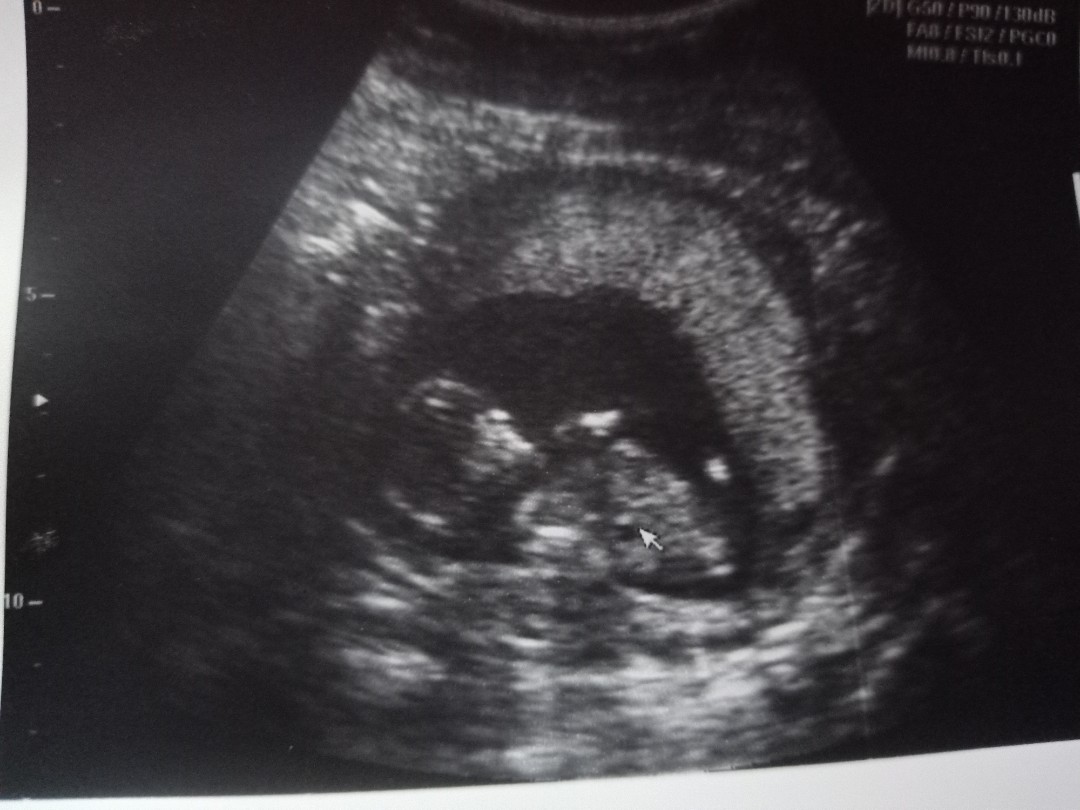

แม่ๆคนไหนมีภาพอัลตร้าซาวด์ประมาณ13วีคบ้างคะ ของเรา13วีค ภาพแบบนี้ค่ะ ดูไม่ออกเลย?